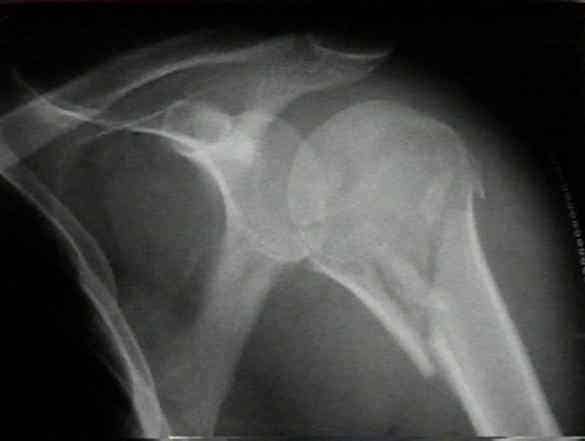

При обращении пациента в травматологический пункт врач проводит осмотр поврежденной конечности, выясняет обстоятельства травмы и уточняет жалобы. После этого для определения точного диагноза травматолог назначает дополнительные исследования. Диагностика позволяет различить перелом шейки от вывиха. Если наблюдаются нарушения чувствительности на наружной стороне плеча и отвисание руки, это может указывать на повреждение подкрыльцового нерва.

Наиболее информативным методом является рентгенография. Снимки делают в двух проекциях: аксиальной, когда изображение получается сверху вниз через подкрыльцовую ямку, и в прямой. При необходимости для более детального анализа травмы может быть назначена компьютерная томография.

Внутрисуставные переломы подтверждаются с помощью ультразвукового исследования. Снимки плечевой кости в аксиальной проекции позволяют выявить наличие боковых смещений отломков. Рентгеновские изображения помогают диагностировать и различать вколоченный перелом плечевой кости от невколоченного.